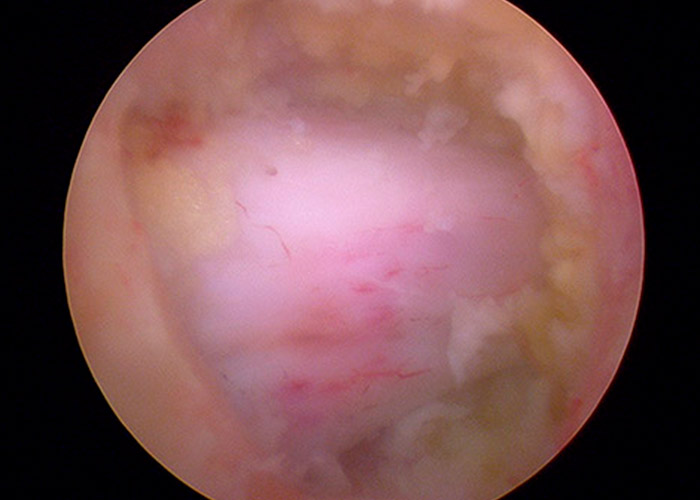

Primero se procede a la identificación del ligamento amarillo y a la identificación de la lámina superior e inferior que limitan la ventana interlaminar.

Se procede a realizar una laminectomía parcial en la lámina superior hasta identificarse la punta de la fase descendente. Se comprueba su adecuada liberación de las estructuras neurológicas en el lado derecho.

Posteriormente se procede a la identificación de la compresión en el canal medular. Se comienza la retirada del ligamento amarillo de la región central para descomprimir las estructuras neurológicas.